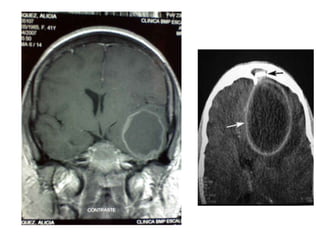

DIAGNÓSTICO

La RNM y la TAC con contraste son los

métodos diagnósticos de

elección, permitiendo además la detección de

un foco parameníngeo responsable y de

complicaciones asociadas.

En la TAC sin contraste, el empiema suele manifestarse como

un área hipodensa sobre un hemisferio o a lo largo de la hoz

cerebral

La RNM proporciona mejores datos que la TAC en relación con la

naturaleza y extensión del empiema subdural.

El empleo de gadolinio como medio de contraste aumenta la

sensibilidad de esta técnica.